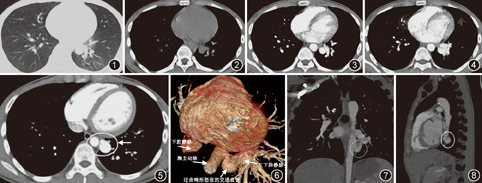

患者男,17岁,因“上呼吸道感染后咳嗽、胸闷15 d”于2014年5月20日入院。患者无发热、咳脓痰及盗汗,无胸痛及咯血,无活动耐力下降,无夜间喘憋或咳嗽加重。无药物食物过敏史,无吸烟史,否认肺结核病史,无吸烟史。外院胸部正侧位片报告示左肺下叶球形病灶,周围见多发卫星灶,考虑肺结核可能性大。入院体检:体温36.6 ℃,血压120/80 mmHg(1 mmHg=0.133 kPa),口唇无发绀,浅表淋巴结无肿大;颈静脉无怒张,胸廓对称,双肺呼吸音粗,未闻及干湿性啰音;心率为72次/min,心律齐,各瓣膜听诊区未闻及杂音;肝脾不大,双下肢无水肿,无杵状指。实验室检查:血常规、凝血常规、肿瘤标记物,G试验、GM试验、PPD试验、降钙素原、ESR、C反应蛋白、新隐球菌抗原检测、痰培养、痰检抗酸杆菌等均无异常。血气分析示:pH值为7.38,PaO2为88 mmHg,PaCO2为73 mmHg,SaO2为97%,AB为25 mmol/L,BB为46 mmol/L,二氧化碳结合力(CO2CP)为26 mmol/L。于2014年5月20日行胸部CT平扫(图1,图2)示左肺炎,左肺下叶占位,建议行CT增强扫描。初步诊断为左肺下叶占位性病变。于2014年5月26日行胸部CT增强扫描,影像科诊断为肺血管畸形(图3,图4)。科内大部分医生诊为肺动静脉瘘(pulmonary arteriovenous fistula, PAVF),少部分医生考虑为肺隔离症,理由是在增强扫描中动脉期畸形血管和降主动脉同时强化,且似乎存在交通支(图5),分析畸形血管血供源于体循环的降主动脉,而非肺动脉。随后组织了影像科、介入科、胸外科进行了院内多学科联合会诊,其中有医生建议行DSA检查,DSA是诊断肺血管畸形的金标准,但为有创检查,有一定的危险性,影像科进行了多层螺旋CT三维血管重建(multislice spiral CT angiography, MSCTA),从各个角度显示畸形血管的空间解剖,血管构成及走向[1](图6、图7、图8),最终诊断为先天性降主动脉肺静脉瘘(congenital descending aorta pulmonary vein fistula, cDAPVF)。